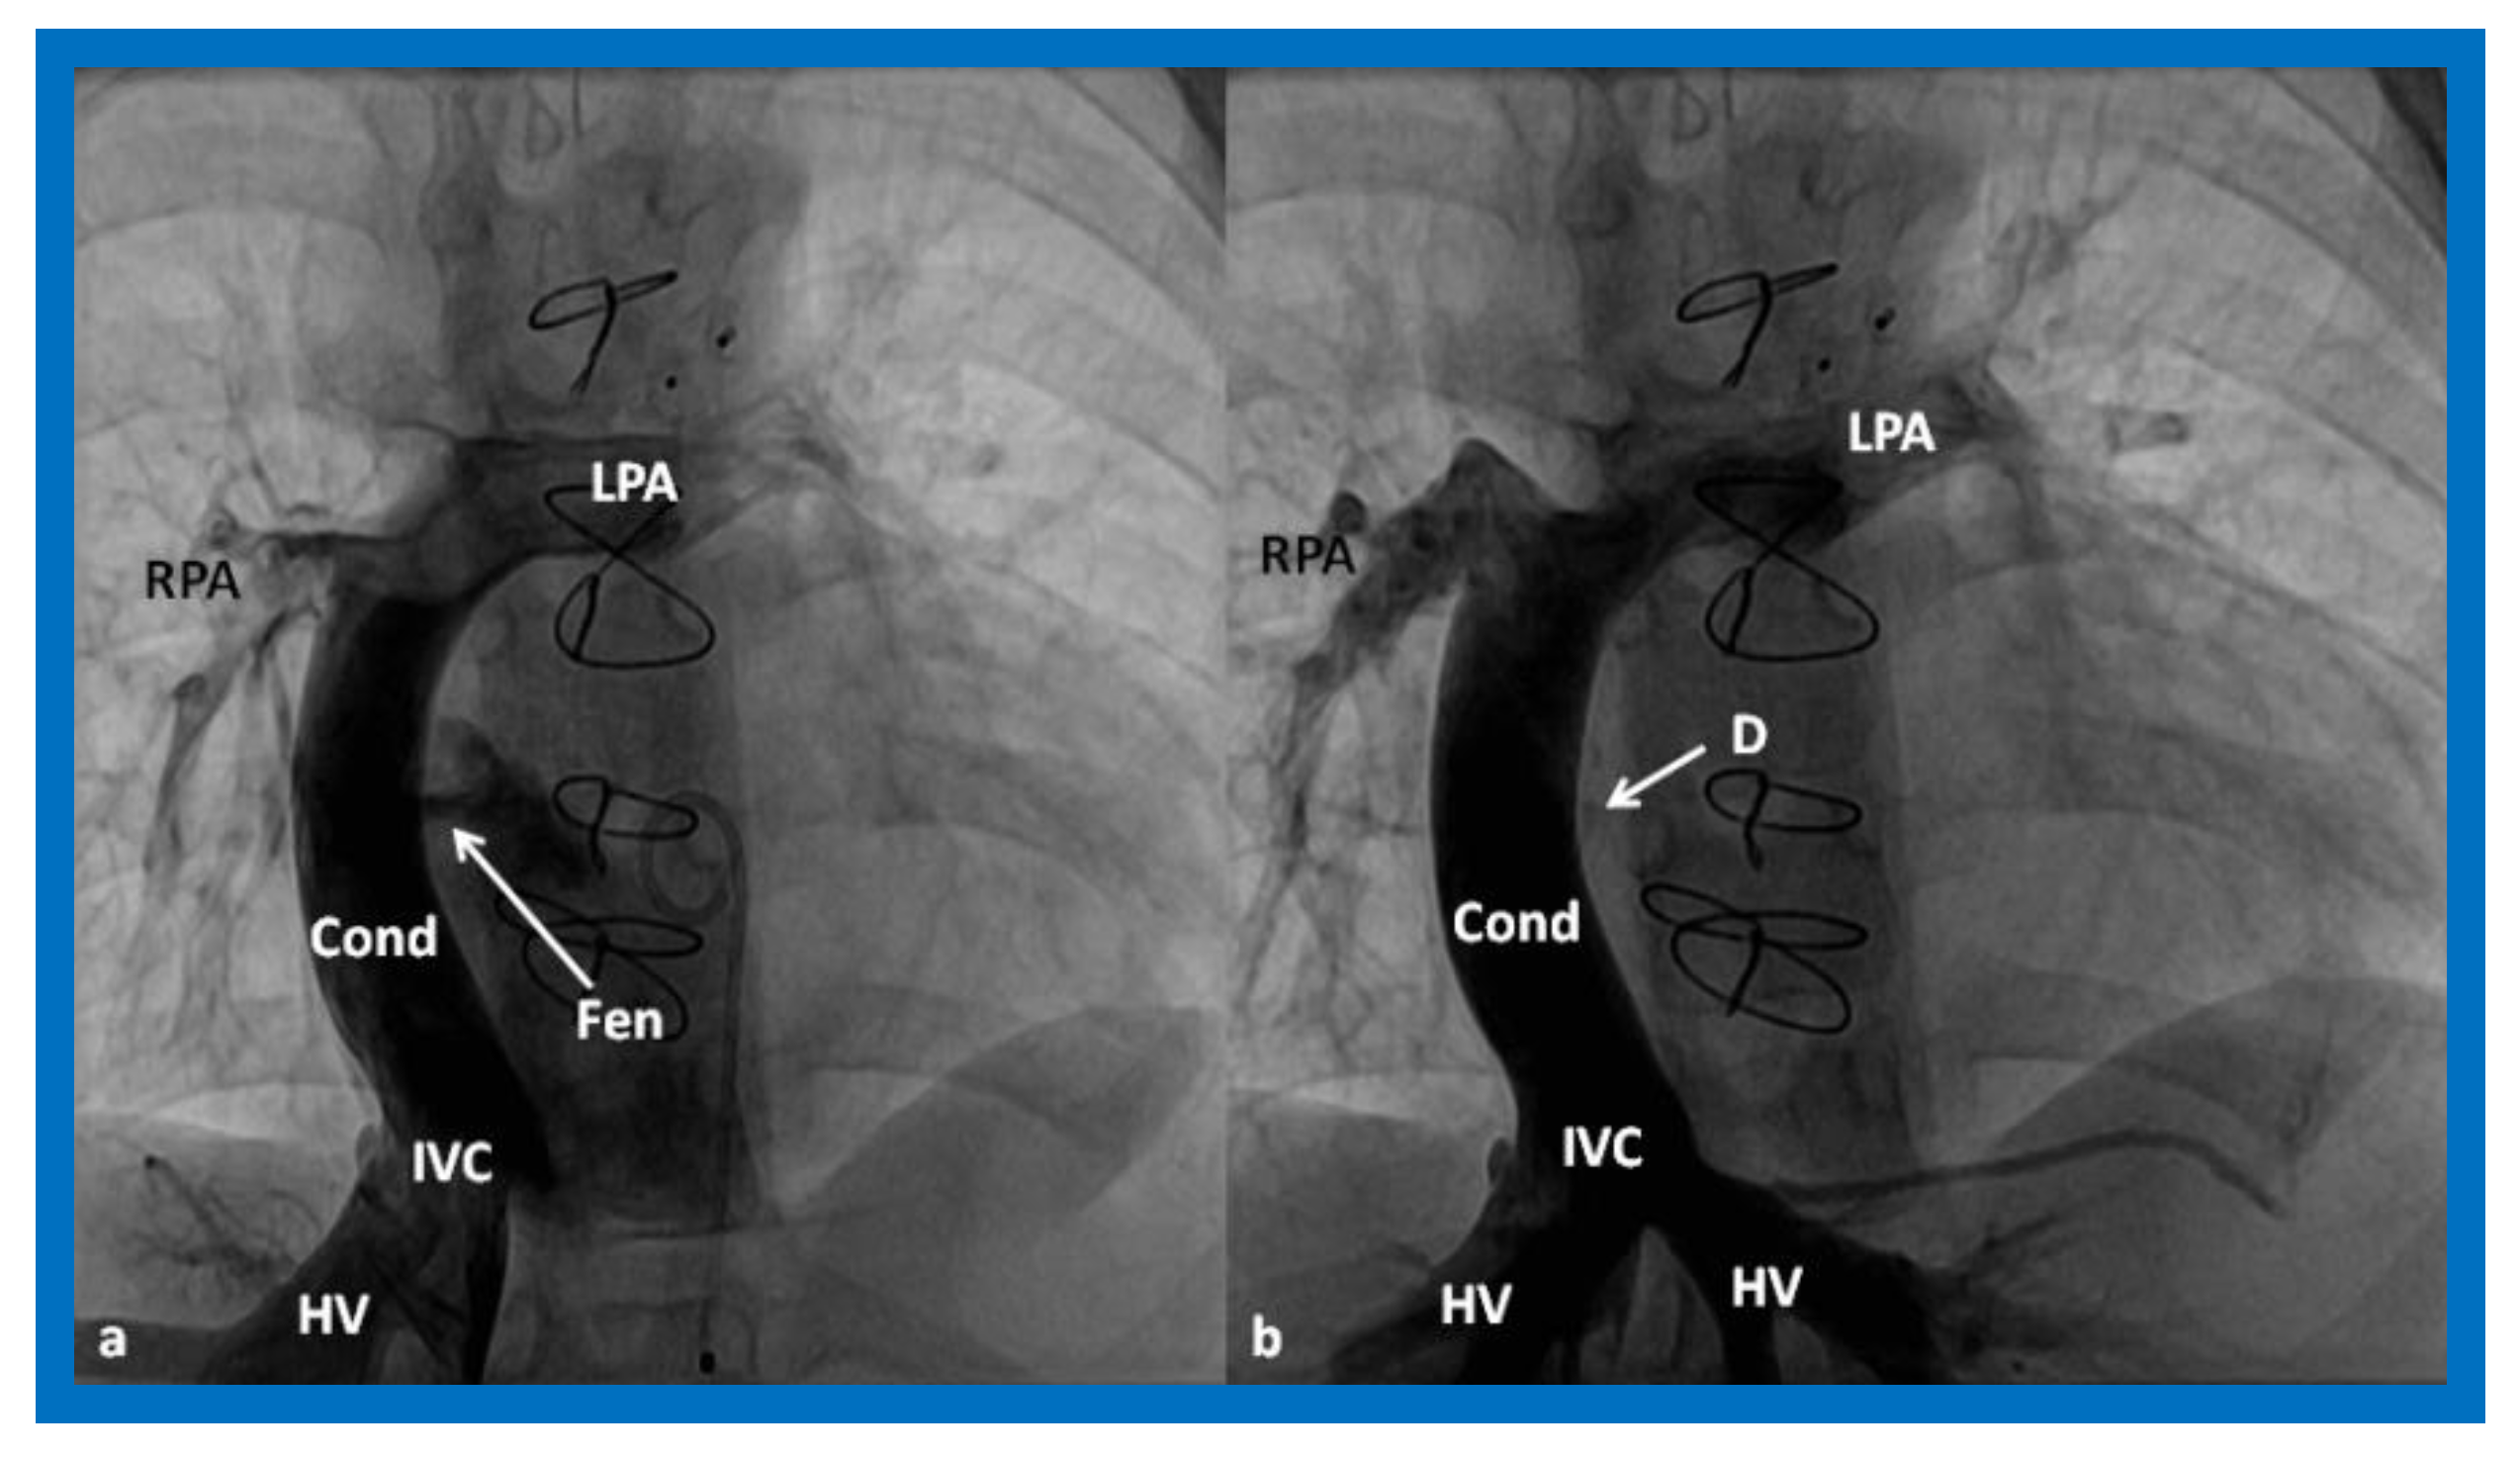

Figure 16.

Cineangiographic frames in postero-anterior (a) and lateral (b) projections, illustrating Stage IIIA of the Fontan procedure in which the inferior vena caval (IVC) blood flow is diverted into the pulmonary arteries via a non-valve conduit (Cond). The flow via the fenestration (Fen) is shown by the arrows in a and b. HV, hepatic veins; LPA, left pulmonary artery; PG, pigtail catheter in the descending aorta; RPA, right pulmonary artery. Modified from Reference [33].

During the Stage IIIB, the fenestration is occluded (Figure 17) by transcatheter methods [33,81,83,84,85], usually 6–12 months following Stage IIIA Fontan. In the past, all previously available ASD occluding devices [81,83,84,85] were used for fenestration closure. However, at the present time, Amplatzer Septal Occluders are the most regularly used devices to accomplish fenestration closures. Any other residual shunts may also be addressed by device closure.

Figure 17.

(a). Cineangiogram in antero-posterior view, illustrating Stage IIIA of the Fontan operation, diverting the inferior vena caval (IVC) blood flow into the pulmonary arteries via a non-valve conduit (Cond). Fenestration (Fen) is shown by the arrow in (a). The Fen is occluded with an Amplatzer device (D), shown by the arrow in (b) (Stage IIIB). HV, hepatic veins; LPA, left pulmonary artery; RPA, right pulmonary artery. Reproduced from Reference [33].